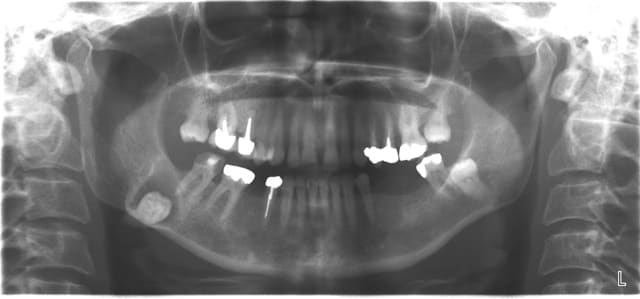

ben tiens dans le même esprit de savoir ce qu'on peut faire si on a le diplôme si on a le droit.

quelle est l'indication de l'AG dans ce cas ?

au passage bel endo sur la 27 et bel amalgame aussi.

ça le pourvoyeur d'AG lui a bien dit après qu'il faudrait refaire tout ça avis que je partage d'ailleurs.il a eu le mérite tout de même de lui dire qu'il fallait au préalable enlever ses 8 avant .